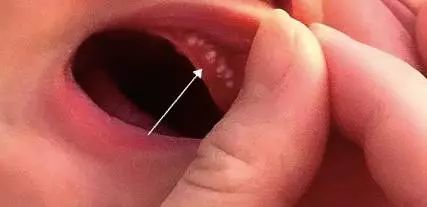

许多妈妈会发现,才几周大的小宝宝,上腭中线附近和牙龈边缘上有黄白色的类似囊泡样的小点,这是长牙了吗?

其实不然,这是一种叫“上皮珠”的东西,俗称“马牙”或“板牙”,并不是真正的乳牙。

马牙是发生在新生儿口腔上腭部位的囊泡,直径在1~3毫米,因为含有角质而呈现黄白色。马牙看起来像是一个个牙齿,但并不是真正的牙齿。